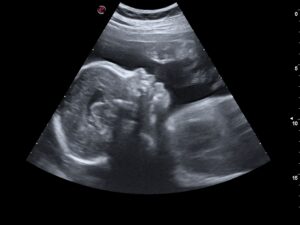

Late / Third Trimester Ultrasound - 28 weeks to term.

These scans evaluate the fetal growth and to estimate the fetal weight. Confirm the position the fetus is lying. (If the head or the bum is down).  We will also verify the position of the placenta.  Doppler studies (ultrasound to determine blood flow) of the umbilical cord and/or the fetus brain can aslo be performed at this stage.